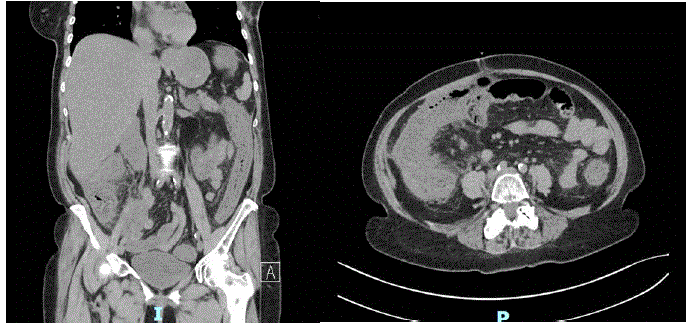

Tomografia de abdome:

Qual é a principal hipótese diagnóstica?